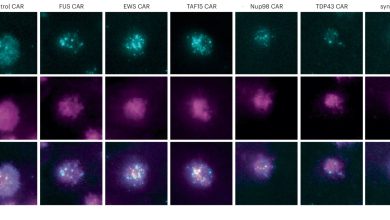

O conjunto de ferramentas de engenharia de proteínas aumenta a eficácia das células CAR-T direcionadas ao sangue e aos cânceres sólidos

Condensação do carro na membrana plasmática fotografada por microscopia TIRF. O carro é marcado por GFP (ciano). A membrana plasmática…